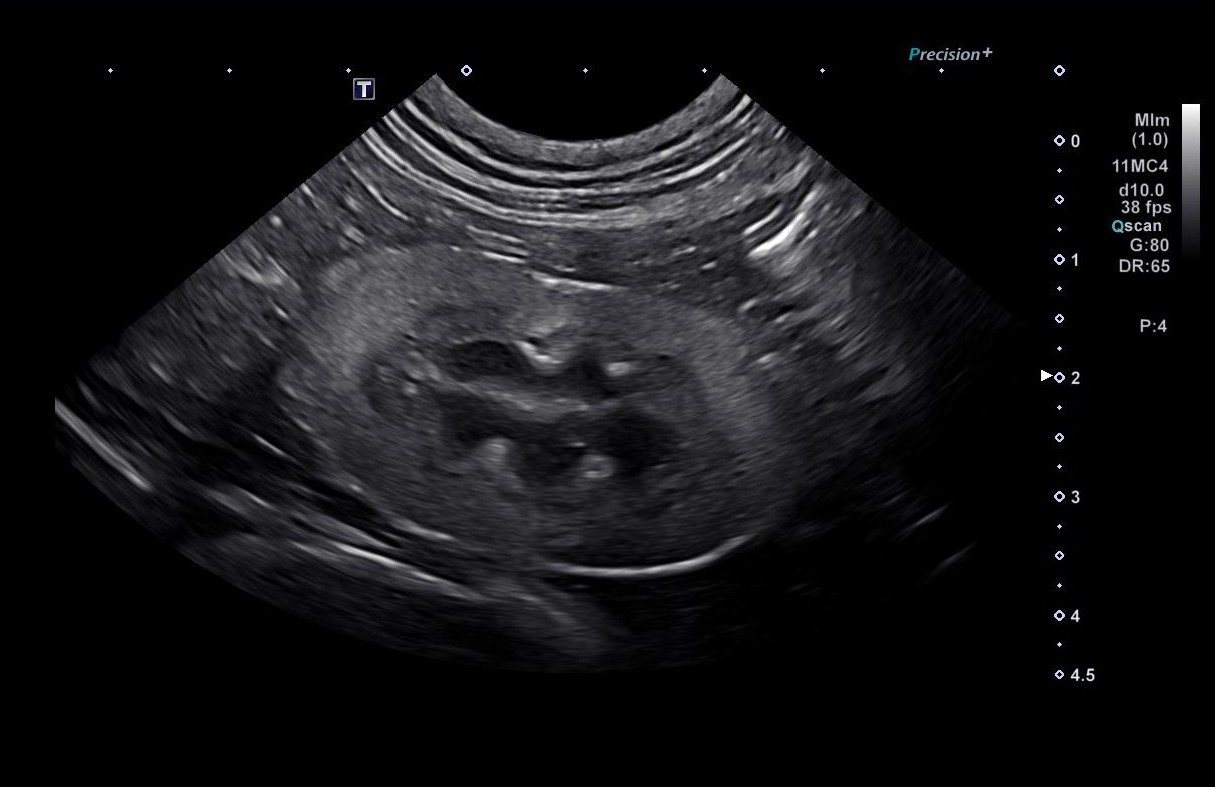

However, CKD can be complex. Some cats may develop additional complications, have atypical lab results, or require specialized imaging such as ultrasound to assess the kidneys’ structure. This is where a veterinary specialty team, such as the VERC Internal Medicine team, can provide advanced care and guidance.

- Requires advanced diagnostics. Ultrasounds, imaging, and specialized lab tests can provide insights that standard bloodwork might miss. This helps identify the exact cause of kidney changes and rule out other conditions.

- Advanced diagnostics. Bloodwork, urinalysis, ultrasounds, and sometimes more specialized testing help pinpoint the severity of kidney disease and rule out other conditions.